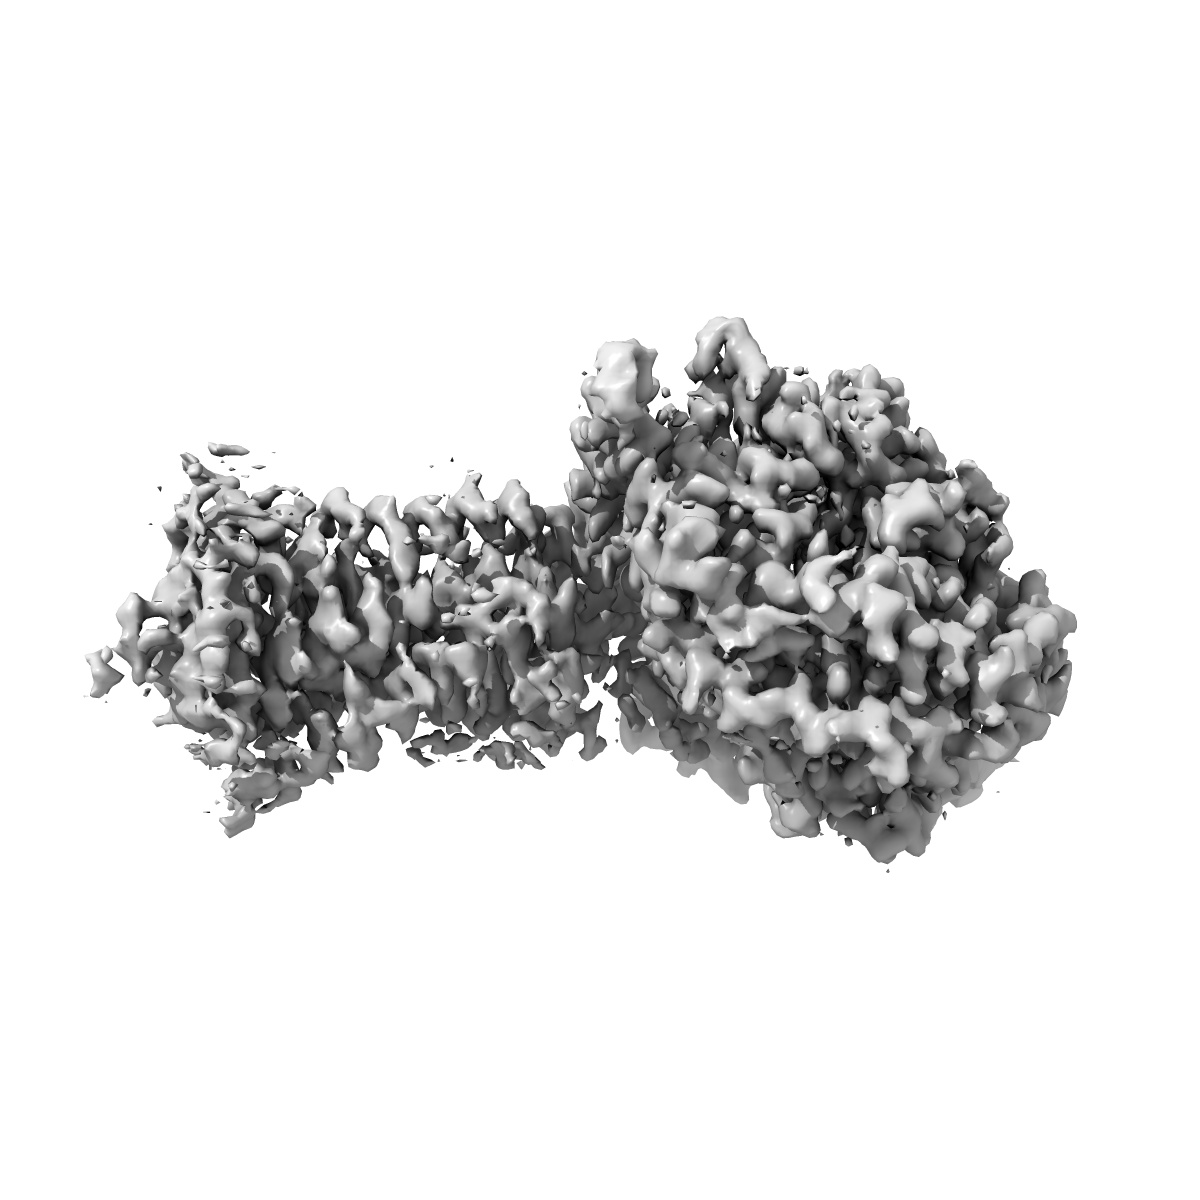

Human Cholecystokinin 1 receptor (CCK1R) Gs complex

Sample: CCK1R/CCK-8/Gas complex

Structures of the human cholecystokinin 1 (CCK1) receptor bound to Gs and Gq mimetic proteins provide insight into mechanisms of G protein selectivity.